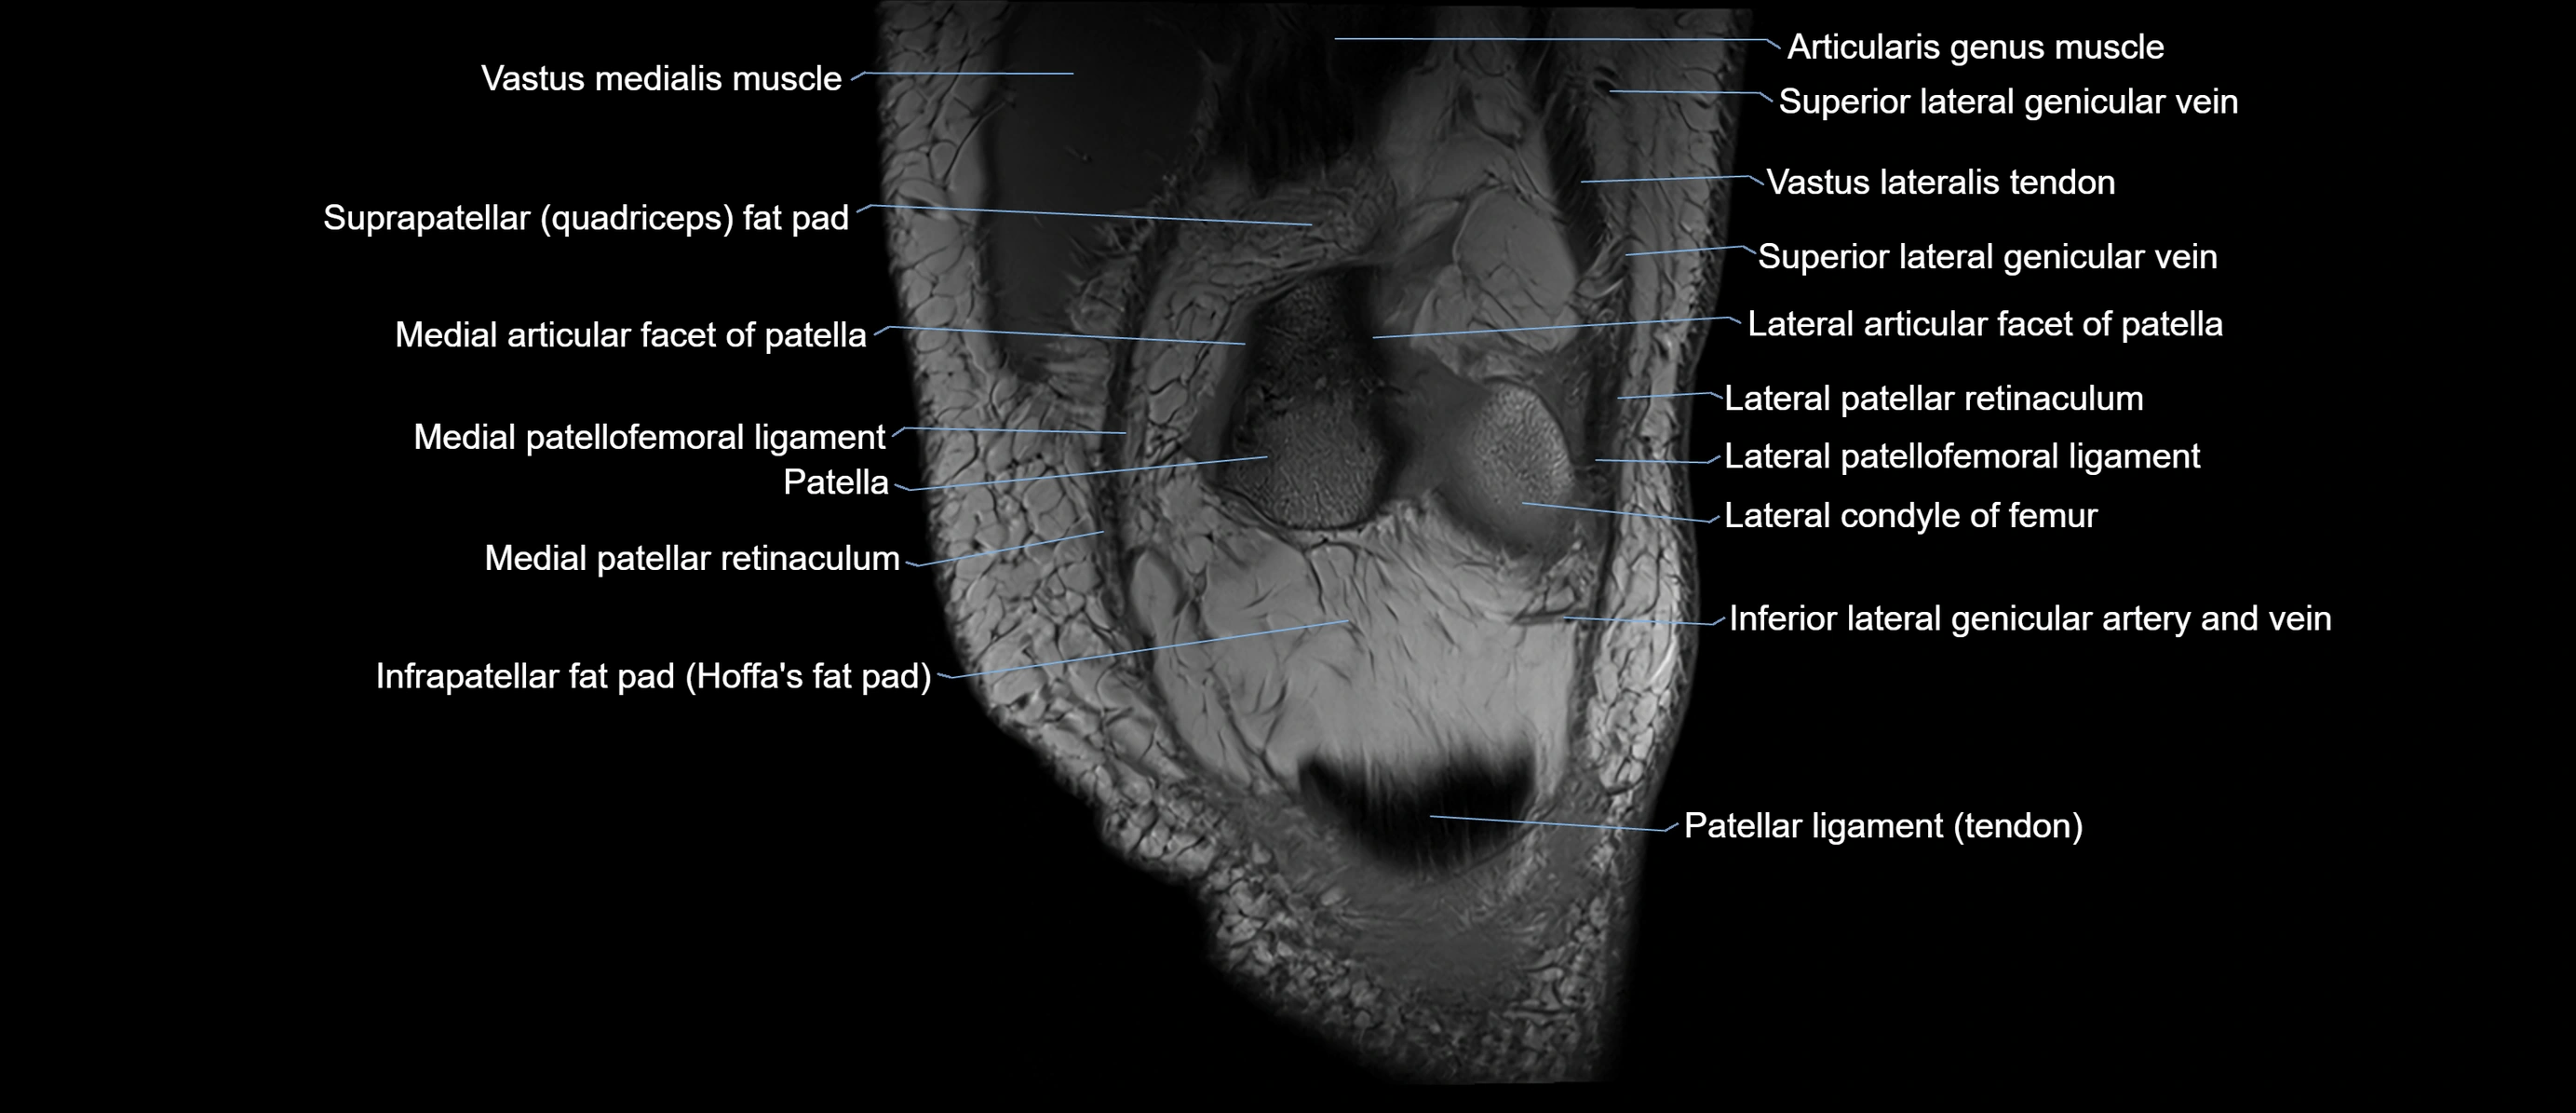

- Lateral articular facet of patella

- Lateral patellar retinaculum

- Lateral patellofemoral ligament

- Medial articular facet of patella

- Medial patellar retinaculum

- Medial patellofemoral ligament

- Patella

- Patellar articular cartilage

- Patellar tendon (patellar ligament)

- Superior lateral genicular vein

- Suprapatellar fat pad

- Infrapatellar fat pad